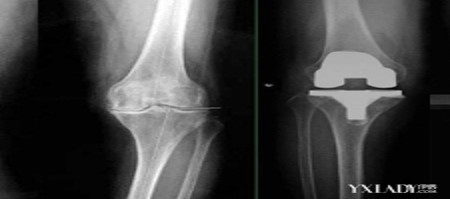

当今时代,人们对于自己的生活质量提出了越来越高的要求,一种治疗严重骨关节炎及膝关节晚期疾病的成熟及有效的手术——人工膝关节置换术,逐渐代替传统仅缓解症状的诊疗手段成为目前治疗各种疾病导致膝关节毁损病变的重要方式。